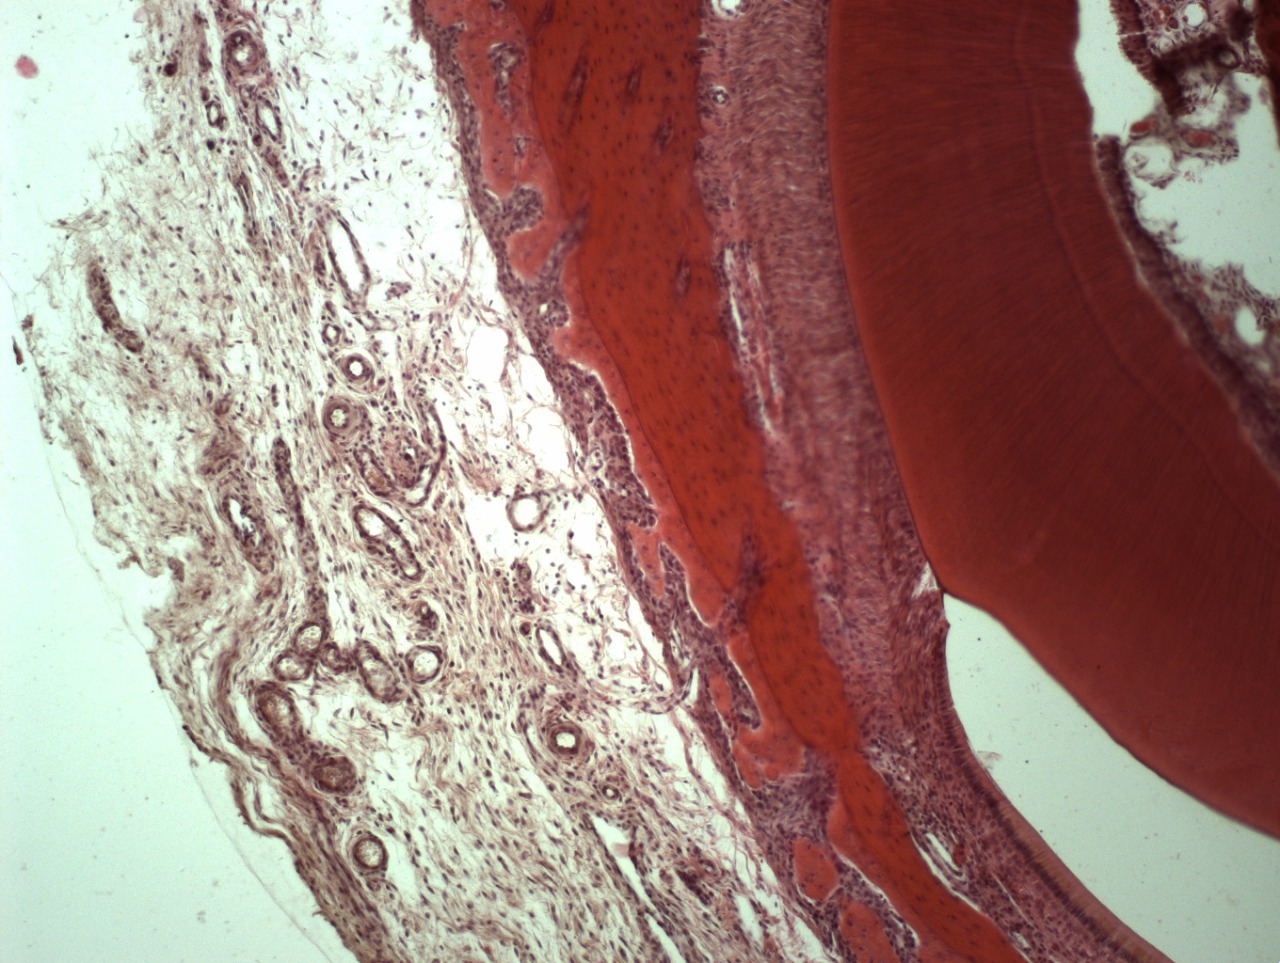

• Например, таким образом удаляются все следы жира, белка, нуклеиновых кислот, мертвых клеток и их компонентов, неколлагеновых белков и прочих соединений. Вследствие такой очистки остается только коллагено-минеральный каркас мертвого межклеточного вещества костной ткани, состав которого стабилен на протяжении всей жизни человека.

• Минерализованную губчатую или кортикальную кость применяют там, где нужно сохранить объем по высоте и ширине, например, при операции поднятия верхнечелюстного синуса или операции имплантации зубов.

• Деминерализованную кость применяют дополнительно для восстановления внутренних костных дефектов: через нее лучше растут кровеносные сосуды, так как она содержит морфогенетический белок (МГБ), но за счет отсутствия минерального каркаса не способна удержать трехмерный объем.

• Алогенный гидроксиапатит используется при увеличении объема более чем на 5-7 мм по высоте. Возможно поднятие на 12, 13 и даже 15 мм.

• Минеральный костный компонент (МКК) «Лиопласт» можно применять в случаях «возрастных» пациентов, наличия в анамнезе различных нарушений минерального обмена в организме.